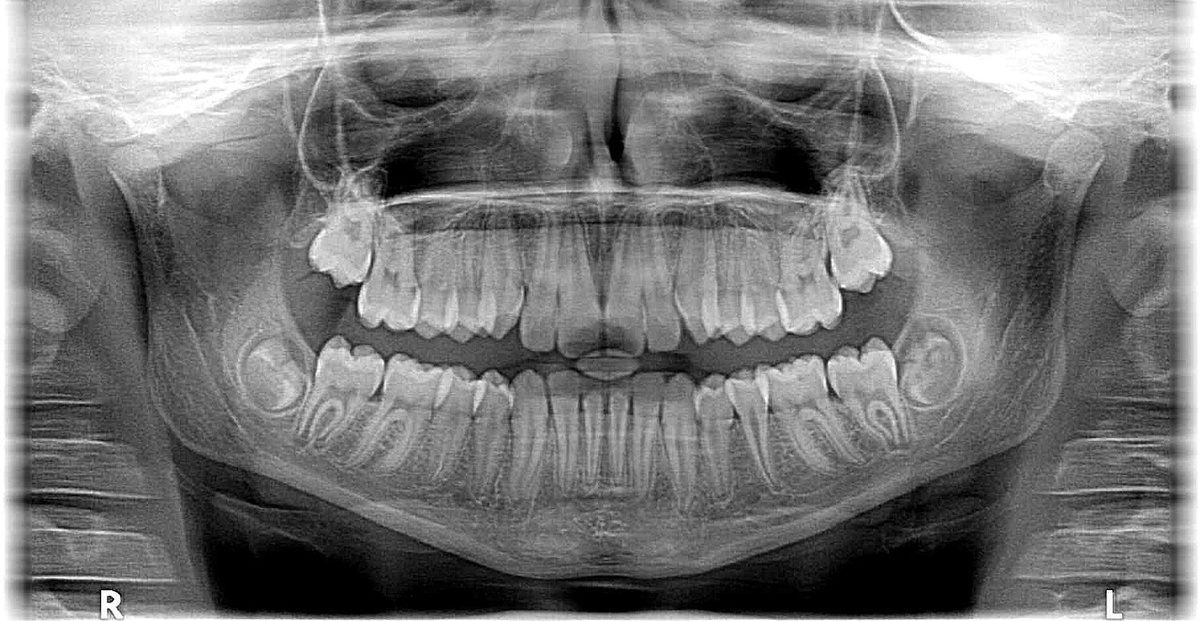

Зубы мудрости, восьмерки – это самые последние зубы в зубном ряду, которые прорезываются в период с 17 до 25 лет, а иногда и позже. Эти зубы получили свое название из-за того, что появляются уже в зрелом возрасте, когда человек, как принято считать, становится мудрее ( но не факт). В отличие от других зубов у них нет предшественников, то есть они не заменяют молочные зубы.

Как правило, восьмерки прорезываются в возрасте от 17 до 25 лет, но этот процесс может начаться и раньше, и позже. В некоторых случаях они могут вообще не прорезаться, оставаясь под десной. Точный возраст, в котором появляются зубы мудрости индивидуален, и зависит от ряда факторов, таких как генетика, общее состояние здоровья, питание и гормональный фон.

• Вертикальное прорезывание. Если восьмерка растет вертикально и у нее есть достаточно места в челюсти, она может прорезаться полностью за 1-2 года.

• Горизонтальное или наклонное прорезывание. Если восьмерка растет под углом или горизонтально, и у нее ограничено пространство, она может прорезываться в течение 2-5 лет, а иногда и дольше.